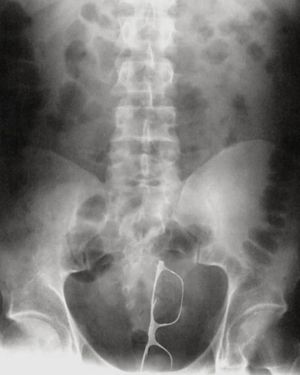

A patient came to the ER with a pair of glases lodged in his rectum. He explained that he slipped and fell directly on them. . The majority of cases of rectal foreign bodies are the result of insertion during erotic activity. Typically found objects are vibrators, dildos, light bulbs, candles, shot glasses, and bottles. Some rectal foreign bodies may have been initially swallowed but later present with complications in the rectum. Patients may be very embarrassed to disclose the circumstances regarding the foreign body insertion, and there may have been multiple attempts at self-removal. Typical clinical findings of a rectal foreign body are pain with defecation, abdominal pain, rectal bleeding, pruritus, and constipation. Delays in seeking medical attention and multiple attempts at self-removal can lead to mucosal edema and muscular spasms, making removal of the object more difficult. FOLLOW us @medicalpedia for more exciting cases!